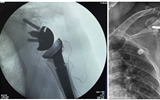

兰大二院骨科完成院内首例创伤性反式肩关节置换手术

[详细]